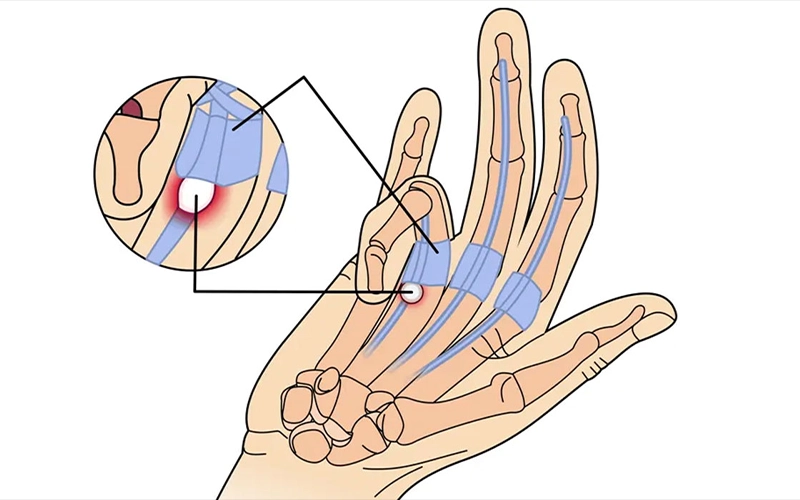

سندروم تونل کارپال (تونل مچ دست)

سندروم تونل کارپال (Carpal Tunnel Syndrome) یکی از شایعترین اختلالات عصبی دست است که در ا...

انگشت ماشهای (تریگر فینگر)

انگشت ماشهای یک بیماری دردناک است که باعث میشود هنگام خم و راست کردن انگشتان، بهویژه شس...